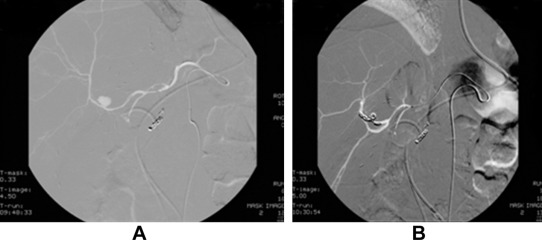

A 51-year-old man underwent living donor liver transplantation for hepatitis B-related liver cirrhosis and hepatocellular carcinoma in 2007. The postoperative course was uneventful and the patient recovered well. He was discharged after 1 month and regularly received immunosuppressant drugs, tacrolimus, and mycophenolatemofetil. The follow-up computed tomography (CT) scan at 3 months post-transplantation revealed biliary anastomotic stricture with moderate dilatation of intrahepatic biliary ducts. Endoscopic retrograde cholangiopancreatography and biliary stenting were carried out to treat the condition. The patient was treated with antibiotics for biliary tract infection caused by Escherichia coli and Pseudomonas aeruginosa. Two weeks after biliary stenting, the patient had an episode of upper GI bleeding. When the patient was subjected to celiac angiography, inflammatory change over the duodenum with subacute bleeding from the gastroduodenal artery was noted. Superselective catheterization and coil embolization were performed to control the bleeding. Three weeks later, the patient had another episode of upper GI bleeding due to hemobilia, as evidenced by endoscopy showing bleeding from the ampullary papilla in the duodenum. Repeated angiography confirmed a pseudoaneurysm arising from the anterior branch of the hepatic artery. Coil embolization of the anterior branch of the right hepatic artery distal and proximal to the neck of pseudoaneurysm was performed ( Fig. 1). Postembolization angiography showed complete occlusion of the segment containing pseudoaneurysm and good flow in the posterior branch. The patient recovered well with no further episodes of bleeding. The patient was discharged 1 month later and regularly followed up until now.

Hepatic artery angiography for Case 1. (A) Pseudoaneurysm arose from the ...

Figure 1.

Hepatic artery angiography for Case 1. (A) Pseudoaneurysm arose from the anterior branch of the right hepatic artery. (B) Pseudoaneurysm was embolized by coil. The liver parenchyma perfusion was preserved from the posterior branch of the right hepatic artery.